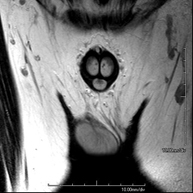

Prova diagnòstica no invasiva que consisteix en l'obtenció d'imatges d'alta definició anatòmica de la regió escrotal mitjançant l'ús d'un camp electromagnètic i ones de ràdio (amb un emissor i un receptor). No utilitza radiació ionitzant. De vegades s'ha d'emprar contrast paragmanètic (Gadolini) per completar l'estudi. S'utilitza per a l'estudi detallat dels testicles, per identificar possibles tumors i diverses patologies i per visualitzar alteracions de les estructures adjacents. - RM peniana

Prova diagnòstica no invasiva que consisteix en l'obtenció d'imatges d'alta definició anatòmica de la regió peniana mitjançant l'ús d'un camp electromagnètic i ones de ràdio (amb un emissor i un receptor). No utilitza radiació ionitzant. De vegades s'ha d'emprar contrast paragmanètic (Gadolini) per completar l'estudi. Normalment es realitza per estudiar la patologia peniana d'origen traumàtic i per visualitzar alteracions de les estructures adjacents.